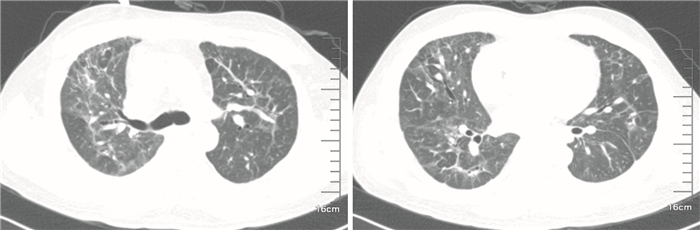

患者入我院后考慮“藥物引起的肺損傷”。結合患者病史及影像學表現,患者吸入“干擾素”后出現上述癥狀,考慮藥物引起的間質性肺纖維化可能性大,支氣管鏡肺活檢排除感染性病變并確診為機化性肺炎,確診當日加用甲基潑尼松龍40 mg靜脈注射qd治療。經全院大會診后,考慮藥物所致的肺損傷,于2014年5月8日開始糖皮質激素沖擊治療:甲基潑尼松龍500 mg靜脈注射qd,連續3 d后改為80 mg qd,連續5 d后改為甲基潑尼松龍片40 mg口服qd,患者癥狀明顯好轉。2014年5月15日復查胸部CT示兩肺多發病灶(圖 4),對比此次治療前的CT檢查結果,病灶有所減少,予以出院。出院后繼續口服甲基潑尼松龍40 mg qd 4周。2014年6月10日復查肺功能:中重度限制性通氣功能障礙,彌散功能輕度下降。胸部CT提示肺部病變進一步好轉(圖 5),繼續激素減量治療。2014年9月10日肺功能:中度限制性通氣功能障礙。2014年12月22日隨訪,患者一般情況可,一般活動不受限,目前甲基潑尼松龍已逐漸減量至4 mg qod,胸部CT檢查示病灶明顯好轉(圖 6)。最終診斷:吸入干擾素所致的機化性肺炎。